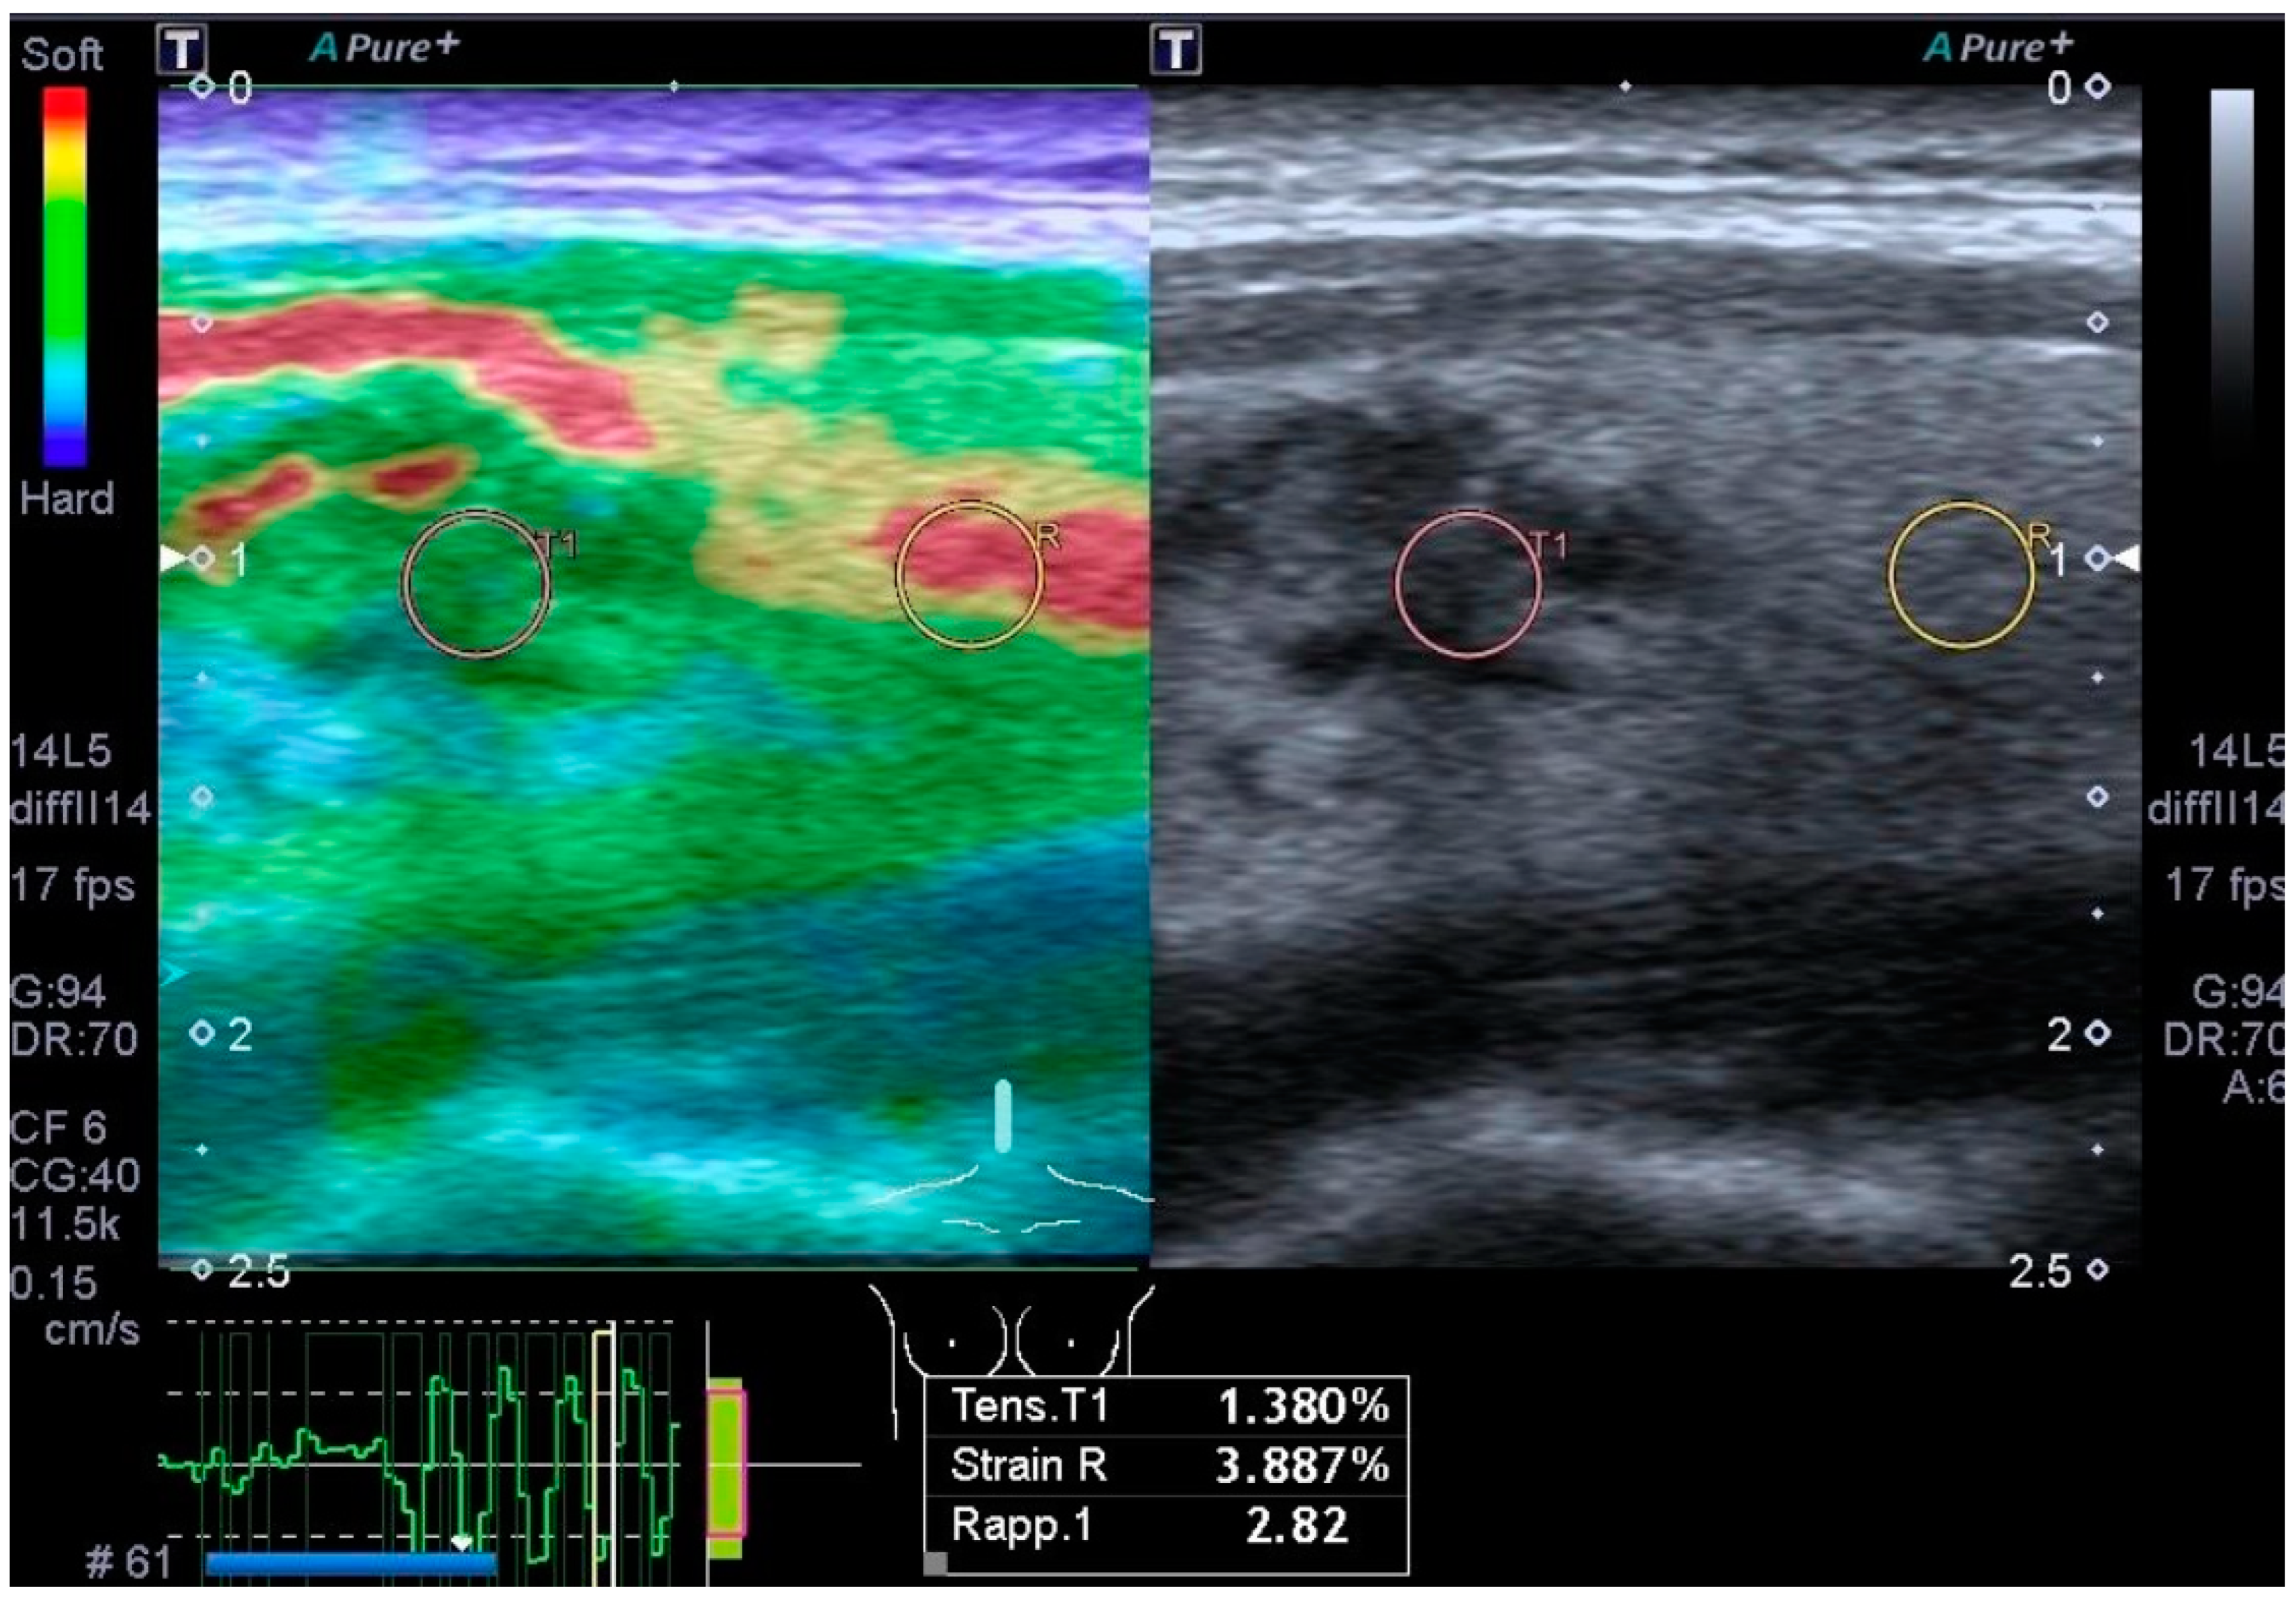

3.4. Elastography

- Cantisani, V.; Grazhdani, H.; Drakonaki, E.; D’Andrea, V.; Di Segni, M.; Kaleshi, E.; Calliada, F.; Catalano, C.; Redler, A.; Brunese, L.; et al. Strain US Elastography for the Characterization of Thyroid Nodules: Advantages and Limitation. Int. J. Endocrinol. 2015, 2015, 908575. [Google Scholar] [CrossRef] [PubMed] [PubMed Central]

- Cantisani, V.; David, E.; Grazhdani, H.; Rubini, A.; Radzina, M.; Dietrich, C.F.; Durante, C.; Lamartina, L.; Grani, G.; Valeria, A.; et al. Prospective Evaluation of Semiquantitative Strain Ratio and Quantitative 2D Ultrasound Shear Wave Elastography (SWE) in Association with TIRADS Classification for Thyroid Nodule Characterization. Ultraschall Med. 2019, 40, 495–503. [Google Scholar] [CrossRef] [PubMed]

- Okasha, H.H.; Mansor, M.; Sheriba, N.; Assem, M.; Abdelfattah, Y.; Ashoush, O.A.; Rakha, M.; Abdelfattah, D.; El-Sawy, S.S.; Elshenoufy, M.; et al. Role of elastography strain ratio and TIRADS score in predicting malignant thyroid nodule. Arch. Endocrinol. Metab. 2021, 64, 735–742. [Google Scholar] [CrossRef] [PubMed] [PubMed Central]